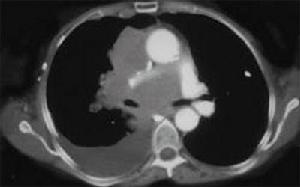

2、CT 或B 超檢查 可見包囊內有分隔結構是有活性包囊的特徵。肺部影像呈圓形包塊,CT 證實包塊內充滿液體,肝外包囊蟲病的血清學檢查陽性率低。根據包蟲囊腫的病理形態與併發症的影像特徵,結合臨床病理分類而劃分為5 型:

(5)、破裂型:①外囊破裂與支氣管相通,少量空氣進入內、外囊之間,形成星月狀透亮影;②內外囊同時破裂,並與支氣管相通,空氣進入內外囊,則出現液平面。其上方有雙層弧的透亮帶,此徵象具有診斷價值;③內外囊完全破裂,內囊塌陷,漂浮於液平面上,使氣液面變得凹凸不平,如“水上浮蓮”也稱“水上浮蓮征”,此徵象為包蟲囊腫破裂的典型CT 表現;④若囊內液體部分被咳出,囊腔縮小,使囊壁摺疊時,其CT 值很高,並難與肺內實質性腫塊鑑別,若囊內容物完全咳出,可形成球形薄壁空腔;⑤肺包蟲囊腫並發感染後表現為囊壁增厚,如有支氣管胸膜瘺時,可引起液氣胸,也可因感染而形成膿胸或膿氣胸;⑥肺外包蟲囊腫,CT 發現肺包蟲囊腫,對診斷很有幫助,對肺包蟲囊腫,禁忌採用胸部穿刺術作為診斷方法,因為穿刺可引起囊液外滲而產生超敏反應或包蟲囊腫播散等嚴重併發症。